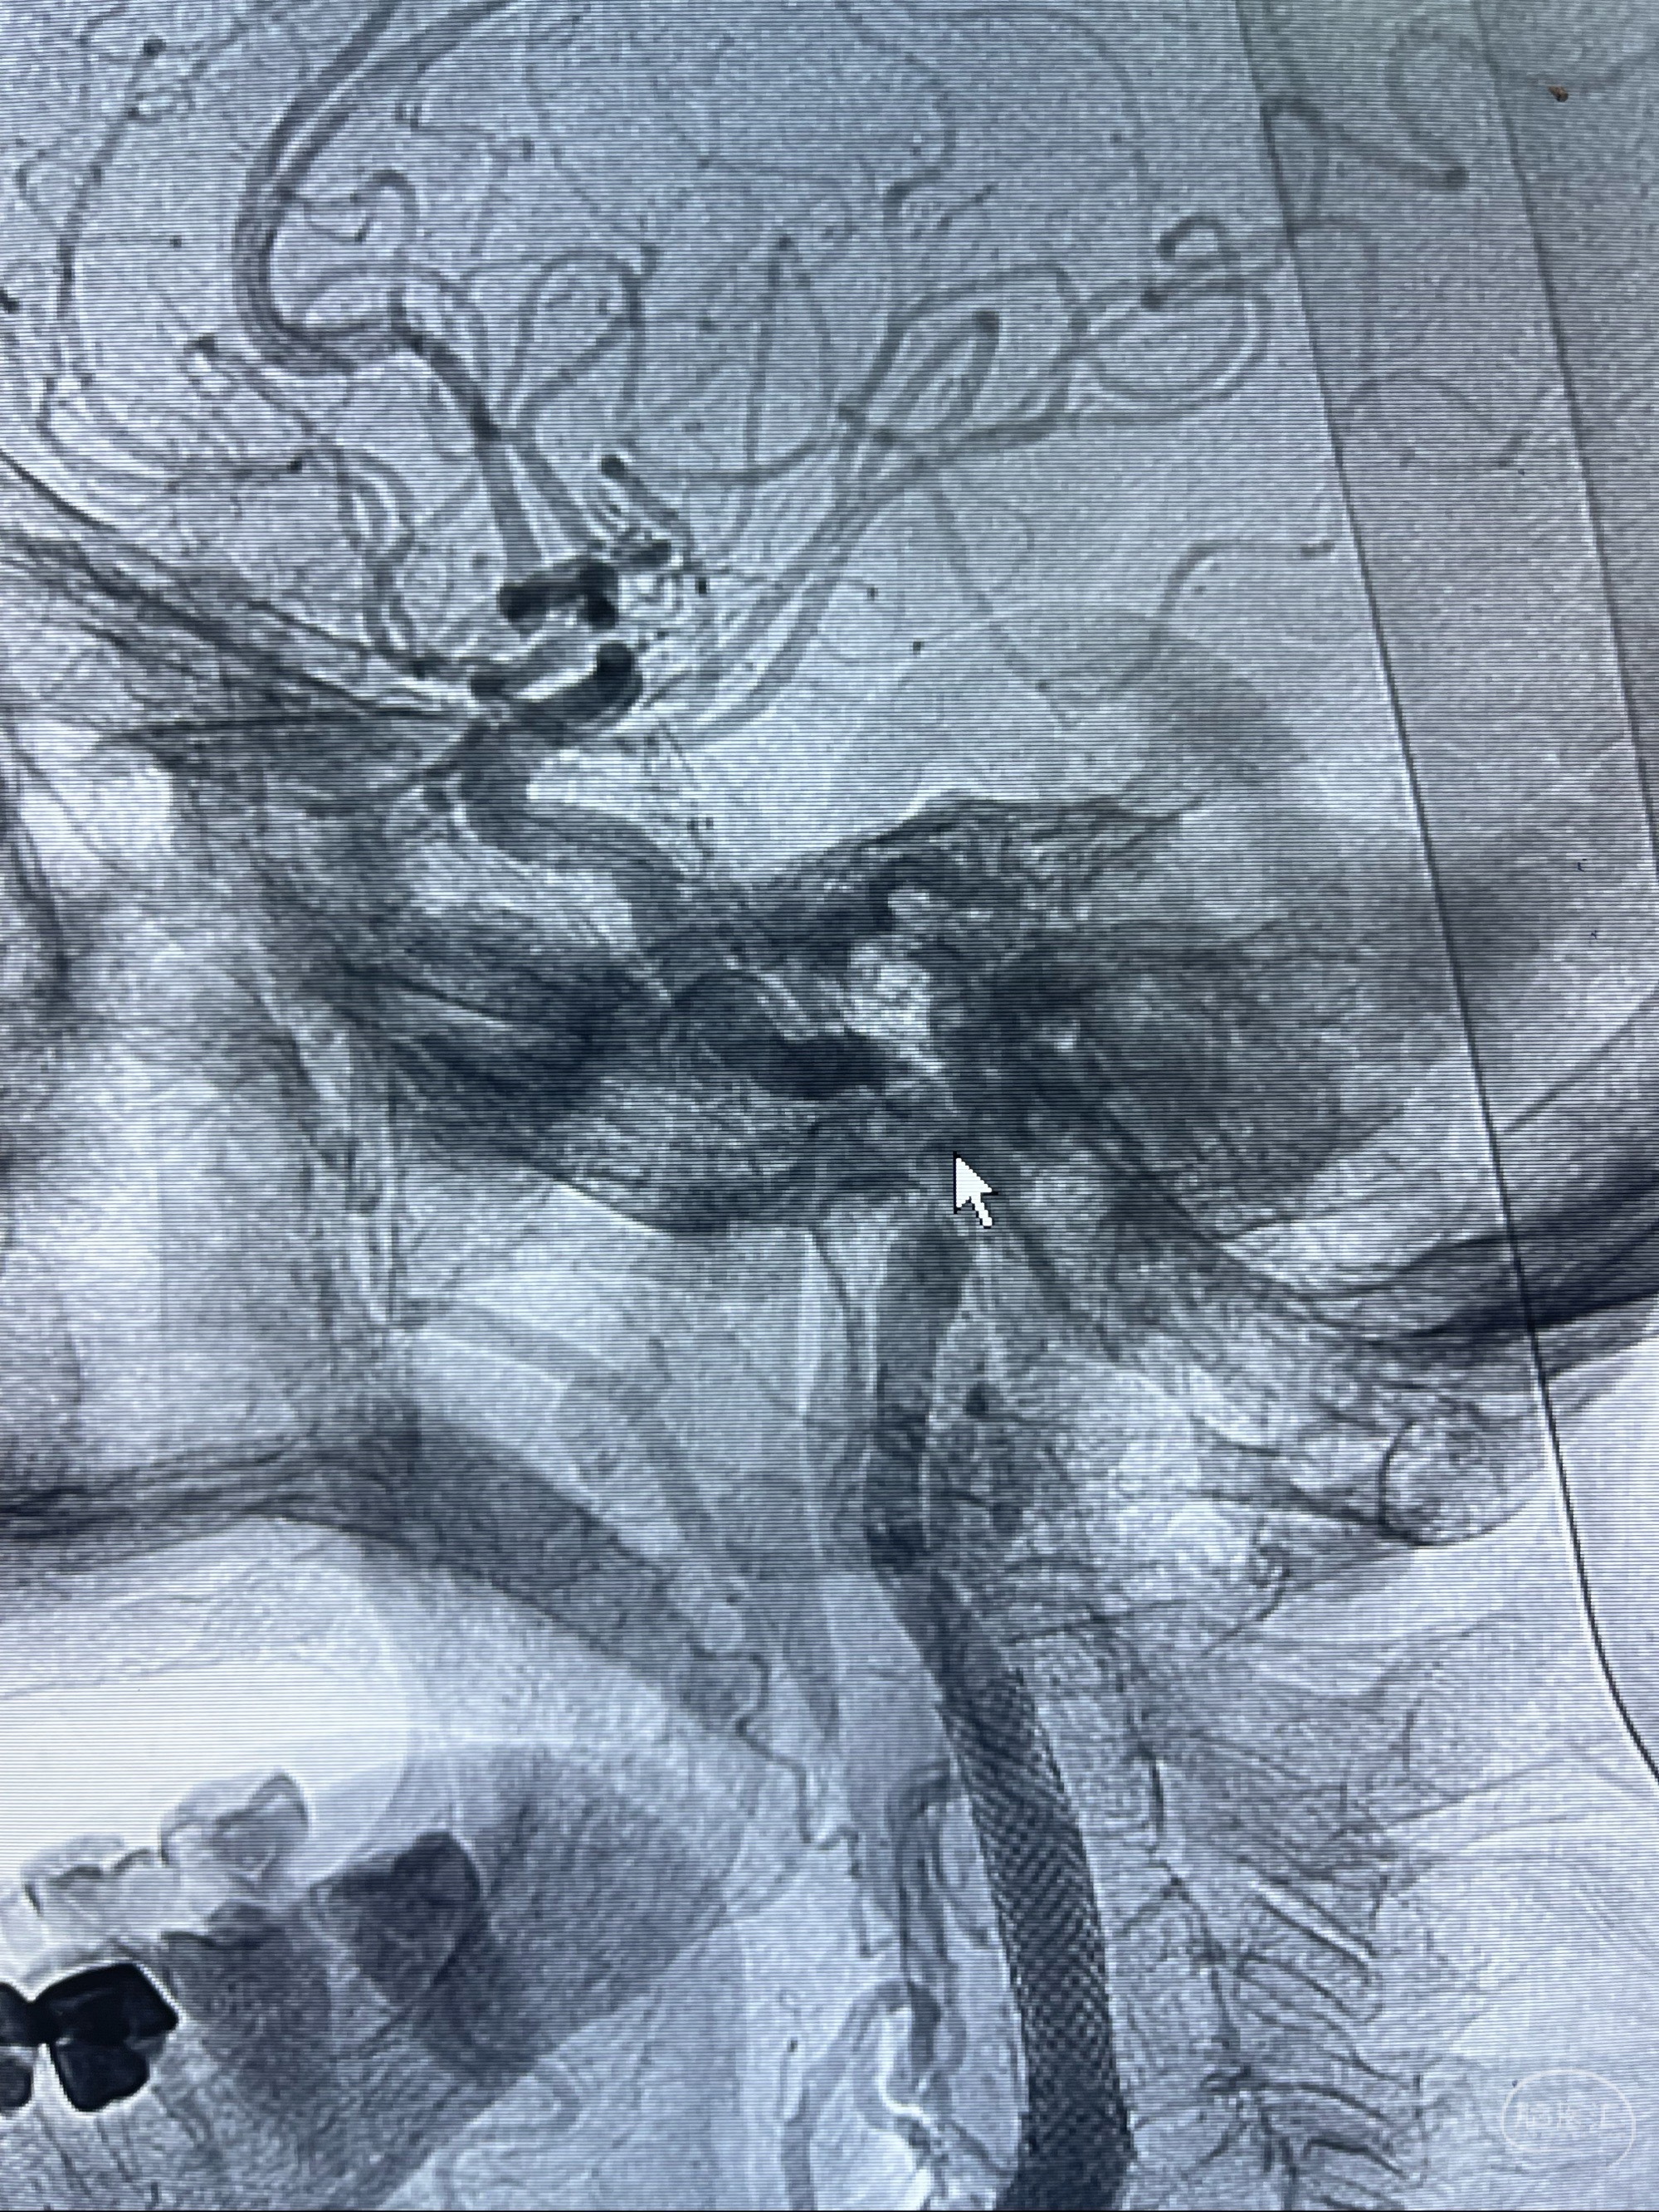

经导引导管造影显示支架远端颈内动脉不规则狭窄伴局部充盈缺损,同时行全身肝素化5ml

路径图下4-20mm球囊在导丝引导下超选择性至狭窄段,以6-8个大气压扩张,持续30s

泄除球囊造影显示局部管腔扩张佳

后移球囊至颈段狭窄段,以8-12个大气压扩张,持续30s后泄除球囊

即刻造影显示狭窄扩张佳